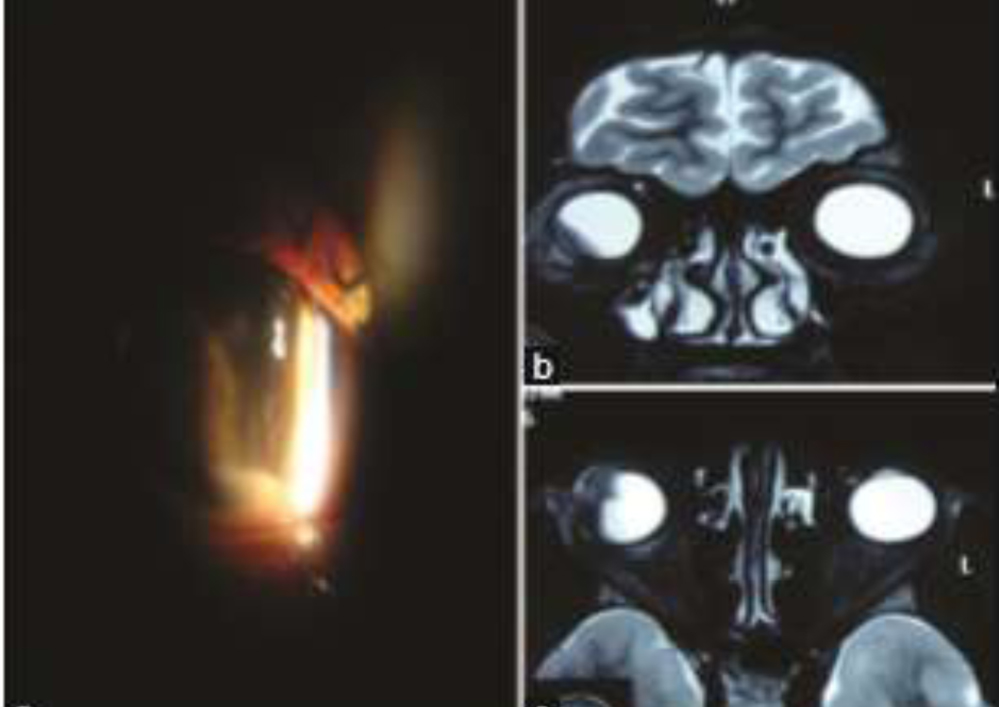

A 23‑year‑old Indian female presented with the chief complaints of dimness of vision, pain and redness in the right eye (OD) for 3 months. The patient was previously treated elsewhere with two posterior sub‑Tenon injections of triamcinolone acetonide given 6 weeks apart. Other medical, surgical, and family histories were unremarkable. On examination, ocular alignment was normal with a visual acuity of counting finger at 3 m in the OD. There was minimal sclerouveitis noted in the inferior‑temporal quadrant of OD. On slit‑lamp examination, OD showed 360° posterior synechiae with anterior chamber flare and cells (+++) with 1 mm hypopyon(Fig 2). There was a suspected mass in the inferior‑temporal quadrant behind the iris, pushing it anteriorly. The left eye examination was unremarkable. B‑scan ultrasound (B‑scan USG) of OD was suggestive of ciliary body mass with adjoining exudative retinal detachment (ERD). USG bio‑microscopy findings were consistent with the findings of B‑scan USG.

Based on the clinical examination and baseline investigations, we came to the differential diagnosis of ciliary body melanoma or similar tumors. Magnetic resonance imaging suggested the possibility of ciliary body melanoma in OD. After obtaining informed consent, enucleation was carried out in OD, and eyeball specimen was sent to ocular pathology laboratory for histopathological analysis. In grossing, there was a grayish‑white‑coloredtumor seen in the inferior‑temporal part of the ciliary body measuring (10.99 × 7.98) mm. Adjoining the grayish‑white ciliary body mass, there was an ERD noted.An eosinophilic mass was seen in the ciliary body with diffuse plasmacytoid cells, with reactive lymphoid follicle and other inflammatory cells.